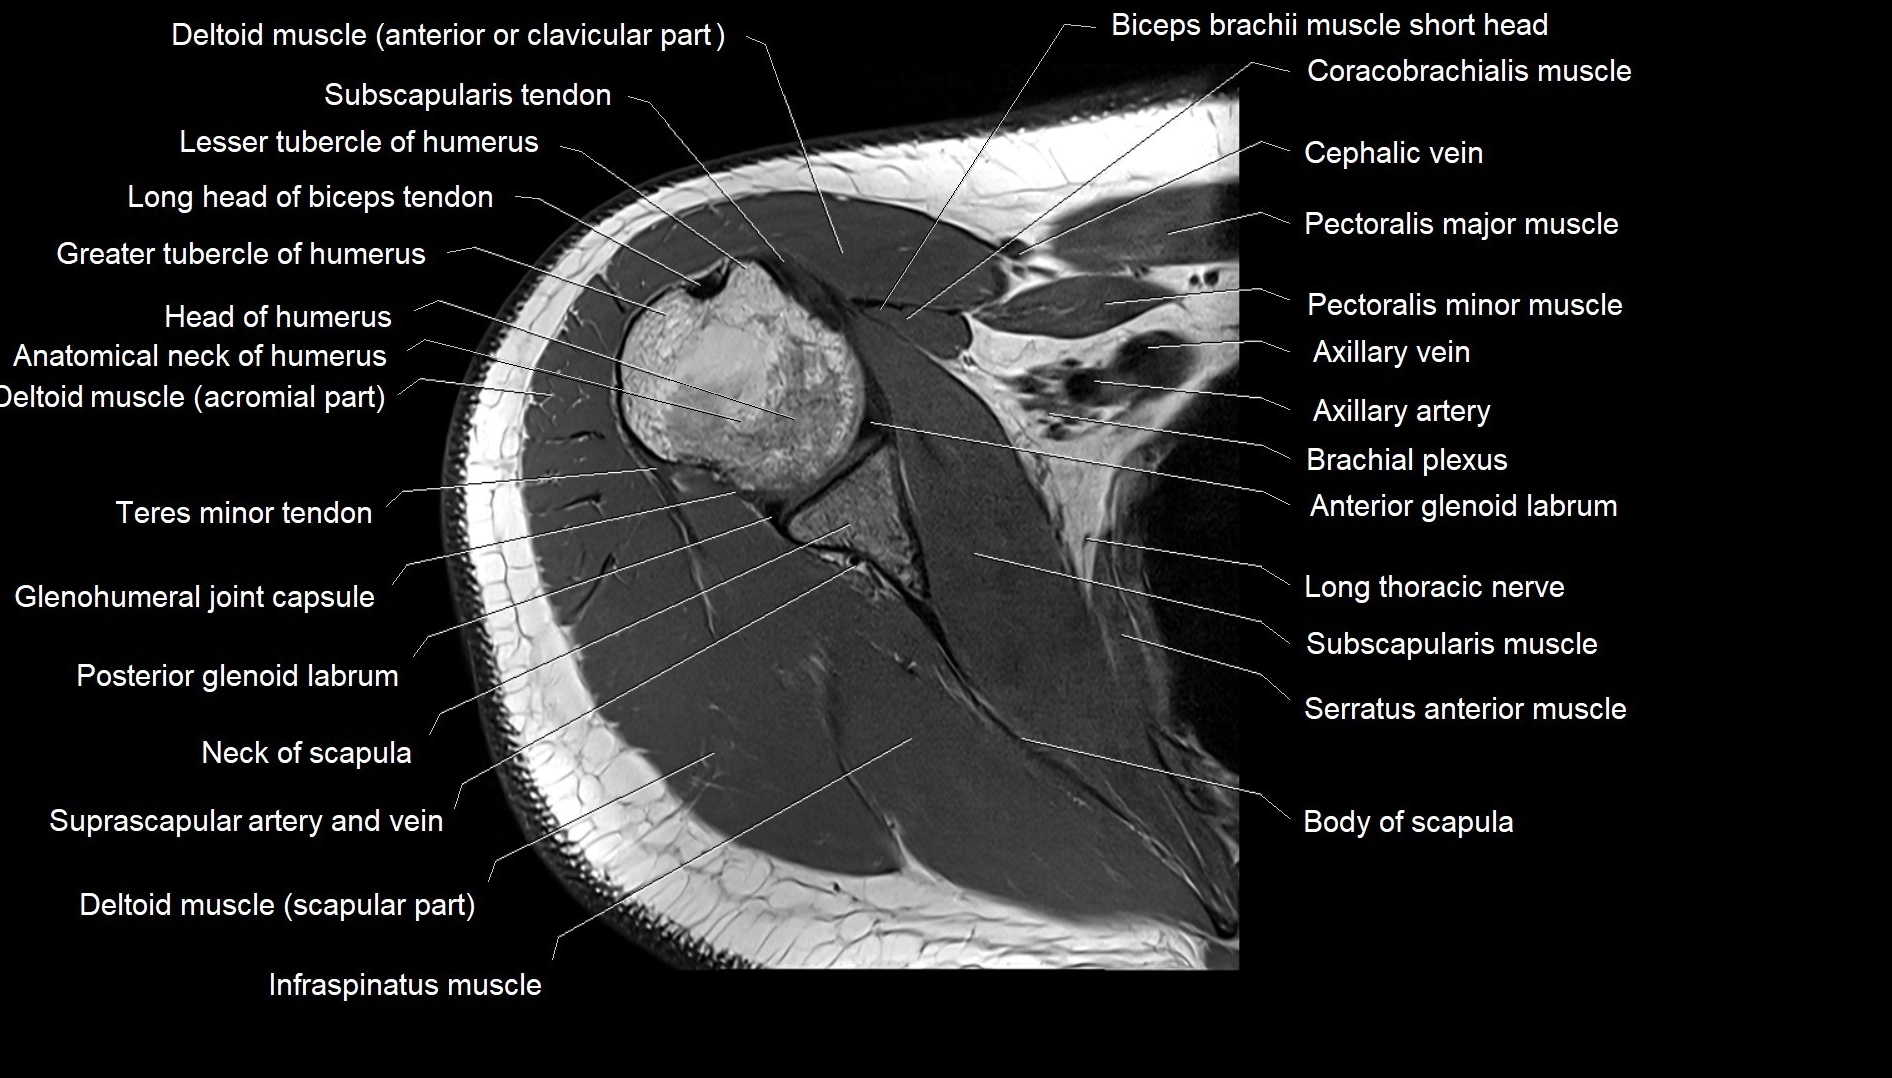

MRI images

image